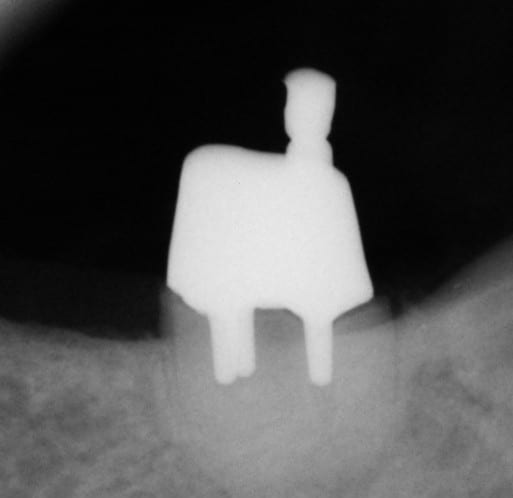

Cette même patiente, pimpante pour ses 90 ans et pleine de gaieté, viens me voir pour son nouvel appareil du bas qu'elle ne supporte pas. Avec surprise, je découvre dessous des chicots abandonnés par son ancien dentiste avec des inflammations gingivales. Radios prises, je lui propose de tenter de les récupérer pour lui réaliser des bridges en remplacement de son appareil, à l'inverse de ce qui se fait habituellement.

La racine résiduelle de la 37 était logée au fond d'un entonnoir gingival au ras de l'os et la 46 était trop délabrée pour la conserver entière. Après quelques séances de gingivoplasties et de tailles, le pari était gagné et les bridges ont pu être scellés, la patiente était radieuse!